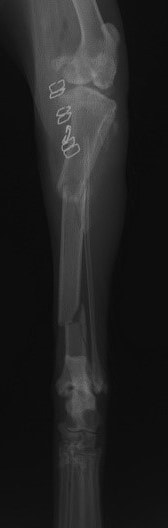

トイプードル 右遠位橈尺骨短斜骨折のALPSによる内固定

ペルシャ猫 11ヶ月齢 雄

他院にて左大腿骨遠位の成長板骨折(salter-harrisⅠ型)が認められており、治療相談を目的として来院。当院にて、キルシュナーワイヤーを用いたピンニングにより骨折部位の整復を行いました。術後の経過は良好で、現在も経過観察中です。

術前レントゲン

術後レントゲン

Arthrex社のターゲティングデバイスを用いてピンニングの位置を調整することで、確実な固定を行っています。当院ではこの手術器具以外にも、人の手術にも使用される様々な器具を導入し、手術精度を高め、また医療メーカーと新しい器具の開発、試作にも取り組んでおります。